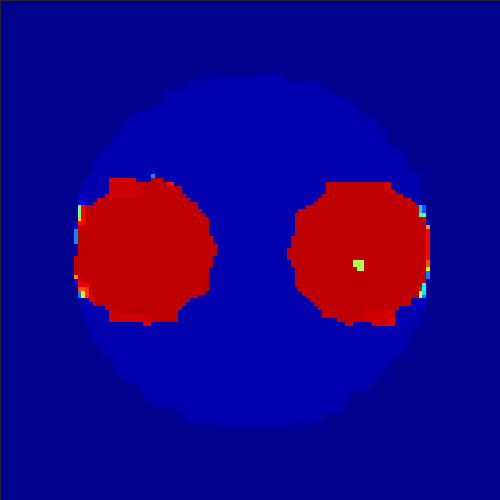

5.2 Monte Carlo Simulation

In order to test the behaviour of the proposed method in a more realistic, random-based test case, we performed a Monte Carlo simulation for dynamic SPECT imaging. First, we created a simple image phantom consisting of an outer and two inner circles which represents the structure of the region of interest (see figure 8(a)). Within those regions we assumed concentration curves over a time period of 90 time steps as displayed in figure 8(b). Based on the tracer intensity in an image frame at each time step, we created a variable number of random decay events (where the number is proportional to the average concentration in one pixel in the whole image frame per time step) with a probability proportional to the concentration in every subregion. They are detected by a virtual double head gamma camera rotating around the patient by 46 degrees per time step, which consists of 374 detector bins. Every simulated decay event is projected onto the scanner and counted by the corresponding detector bin.

In two different tests we fixed the number of events counted by the detector equal to (resp. ) times the average concentration in one pixel. The resulting sinogram images of the accumulated counts in each bin are shown in figure 9.

Based on the sinogram data we applied the proposed algorithm in order to reconstruct the original image sequence. The results for both test cases are shown in figure 10.

As one can see, the method is able to reconstruct the regions properly, even in case of a low count number. Within a number of iterations (average of 100 outer and 10000 inner iterations), the algorithm presents a reasonable reconstruction of the region of interest and the corresponding regional tracer concentration curves. Here, the parameters were not optimized as in the case of the synthesized data sets in the previous section, but kept fixed as , and . With futher optimized parameter values one could possibly provide even better results.